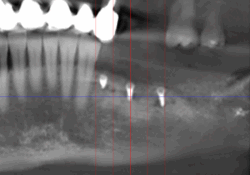

Reprise de traitement implantaire

La reprise de traitement désigne le processus par lequel un patient reprend des soins après un échec de traitement implantaire ou lorsque des complications surviennent. Voici les étapes typiques d’une reprise :

En cas d’échec ou de complications, la reprise de traitement implique une évaluation diagnostique, une extraction (si nécessaire), une cicatrisation, puis une reconstruction osseuse suivie d’une nouvelle implantation.